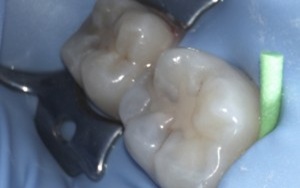

These pictures are a case example of a cosmetic tooth-coloured filling done here at Cornerstone Dental.

Step 2